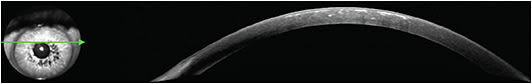

Examination showed granular deposits in the anterior stroma of both corneas (Figure 1) consistent with GCD2. An anterior-segment (AS)-OCT of the right eye revealed granular and hyaline deposits throughout the anterior and mid stroma. AS-OCT is paramount for determining the depth of granular deposition in the cornea.

Due to the depth of the deposits, the patient underwent an uncomplicated DALK, and had complete resolution of his stromal opacities (Figure 2). Histopathology confirmed granular and hyaline deposits in the diseased corneal specimen consistent with GCD2.